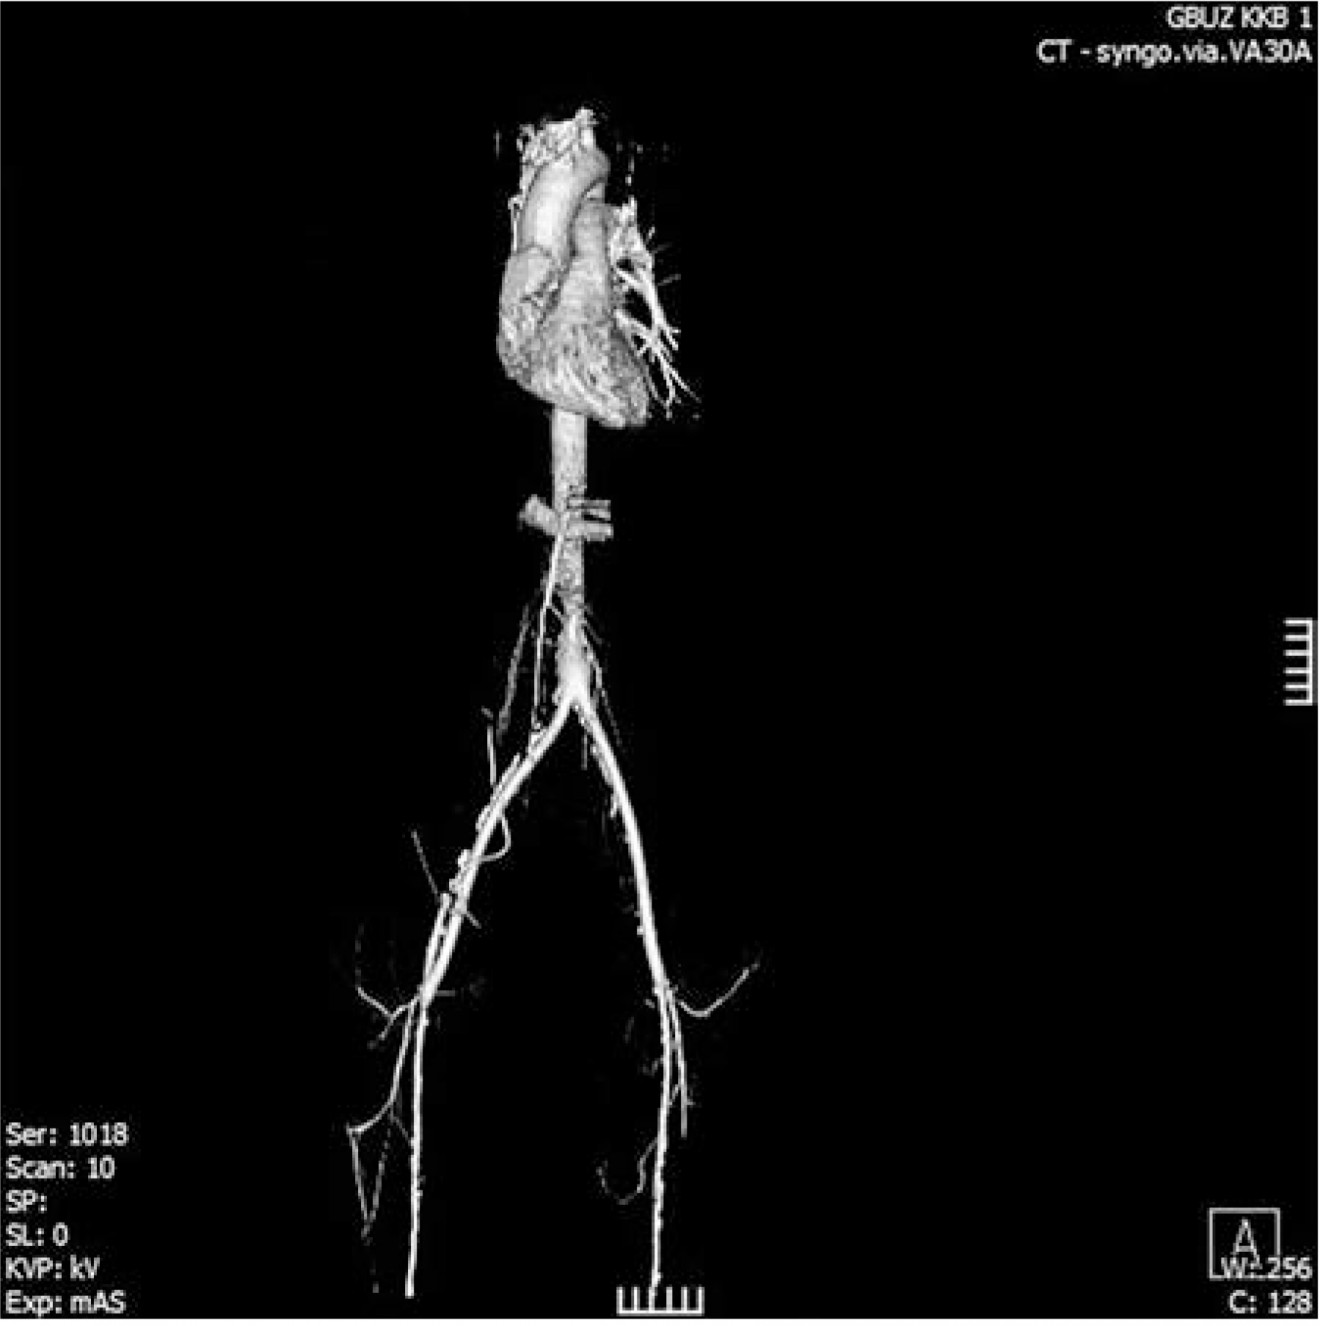

Послеоперационный период протекал без особенностей и осложнений. На вторые сутки после операции пациент переведен в общую палату из ОРИТ, вертикализирован. Самостоятельный стул получен через сутки после операции. На третьи сутки удалены дренажи (рис. 6), выполнена МСКТ с внутривенным контрастированием с шагом 1 мм с целью послеоперационного контроля (рис. 7). Конструкция проходима, препятствий для кровотока нет.

Рис. 7. 3D-реконструкция МСКТ с внутривенным контрастированием после оперативного вмешательства.